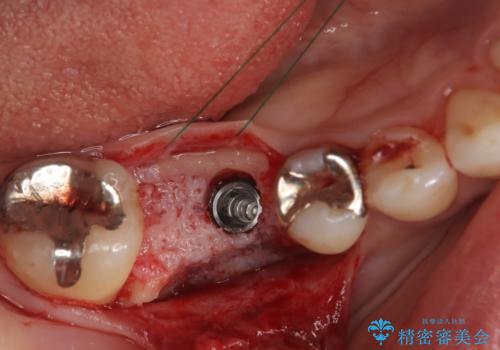

骨の量は十分あったため、比較的短期間で治療は終了しました。

安定した咬み合わせとなり、痛みもなく安心して噛めるようになりました。